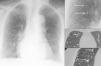

Mujer de 85 años con antecedentes de osteoporosis y fractura vertebral dorsal tratada mediante vertebroplastia. En una radiografía de tórax por protocolo preanestésico para la realización de una nueva vertebroplastia se identificaron múltiples opacidades lineales ramificadas hiperdensas en ambos campos pulmonares que seguían el curso de las estructuras vasculares (fig. 1). Se comprobó en pruebas radiológicas previas la ausencia de los hallazgos descritos, planteándose el diagnóstico de embolismo pulmonar por el paso de cemento a la circulación sistémica. En la TC de alta resolución (TCAR) se confirmó la existencia de múltiples estructuras lineales hiperdensas (cemento) en el interior de las arterias pulmonares segmentarias de varios lóbulos pulmonares.